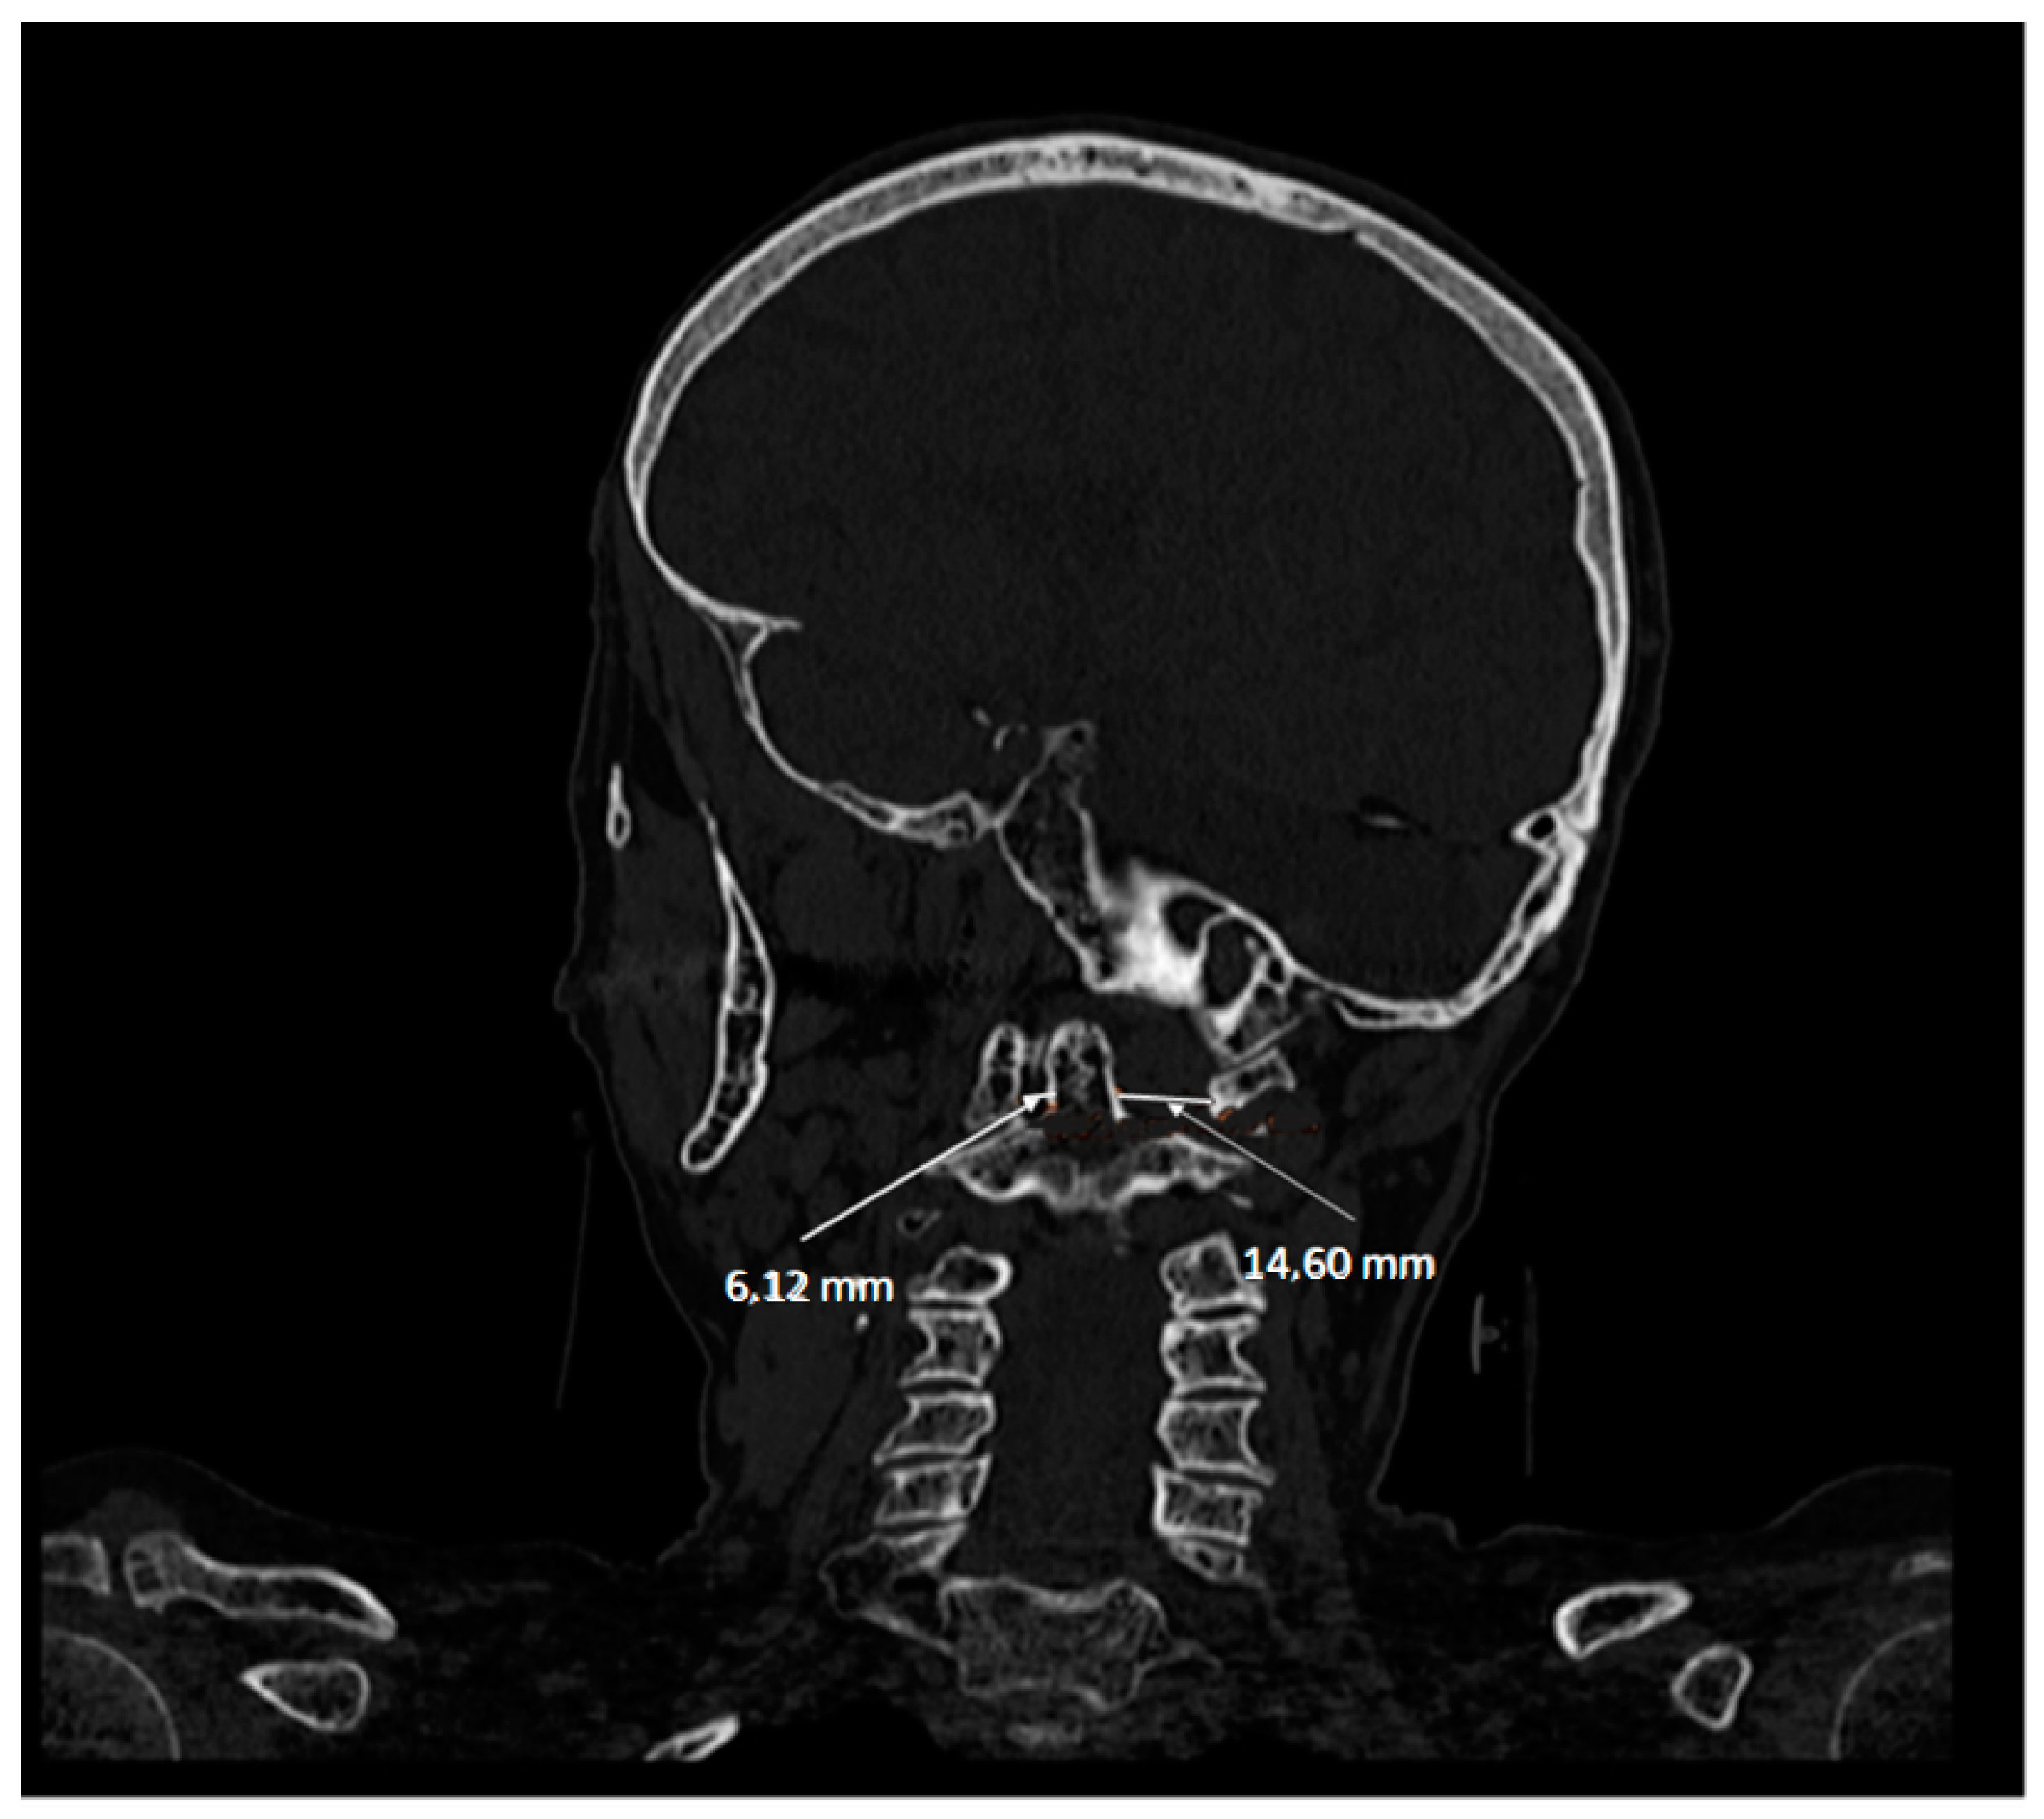

5.2. Computed Tomography (CT)